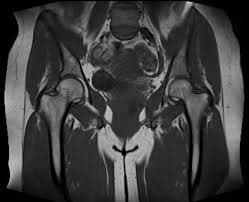

Get rid of your pain with Hip MRI! Fast and reliable MRI imaging service with expert radiologists. Early diagnosis, healthy life!